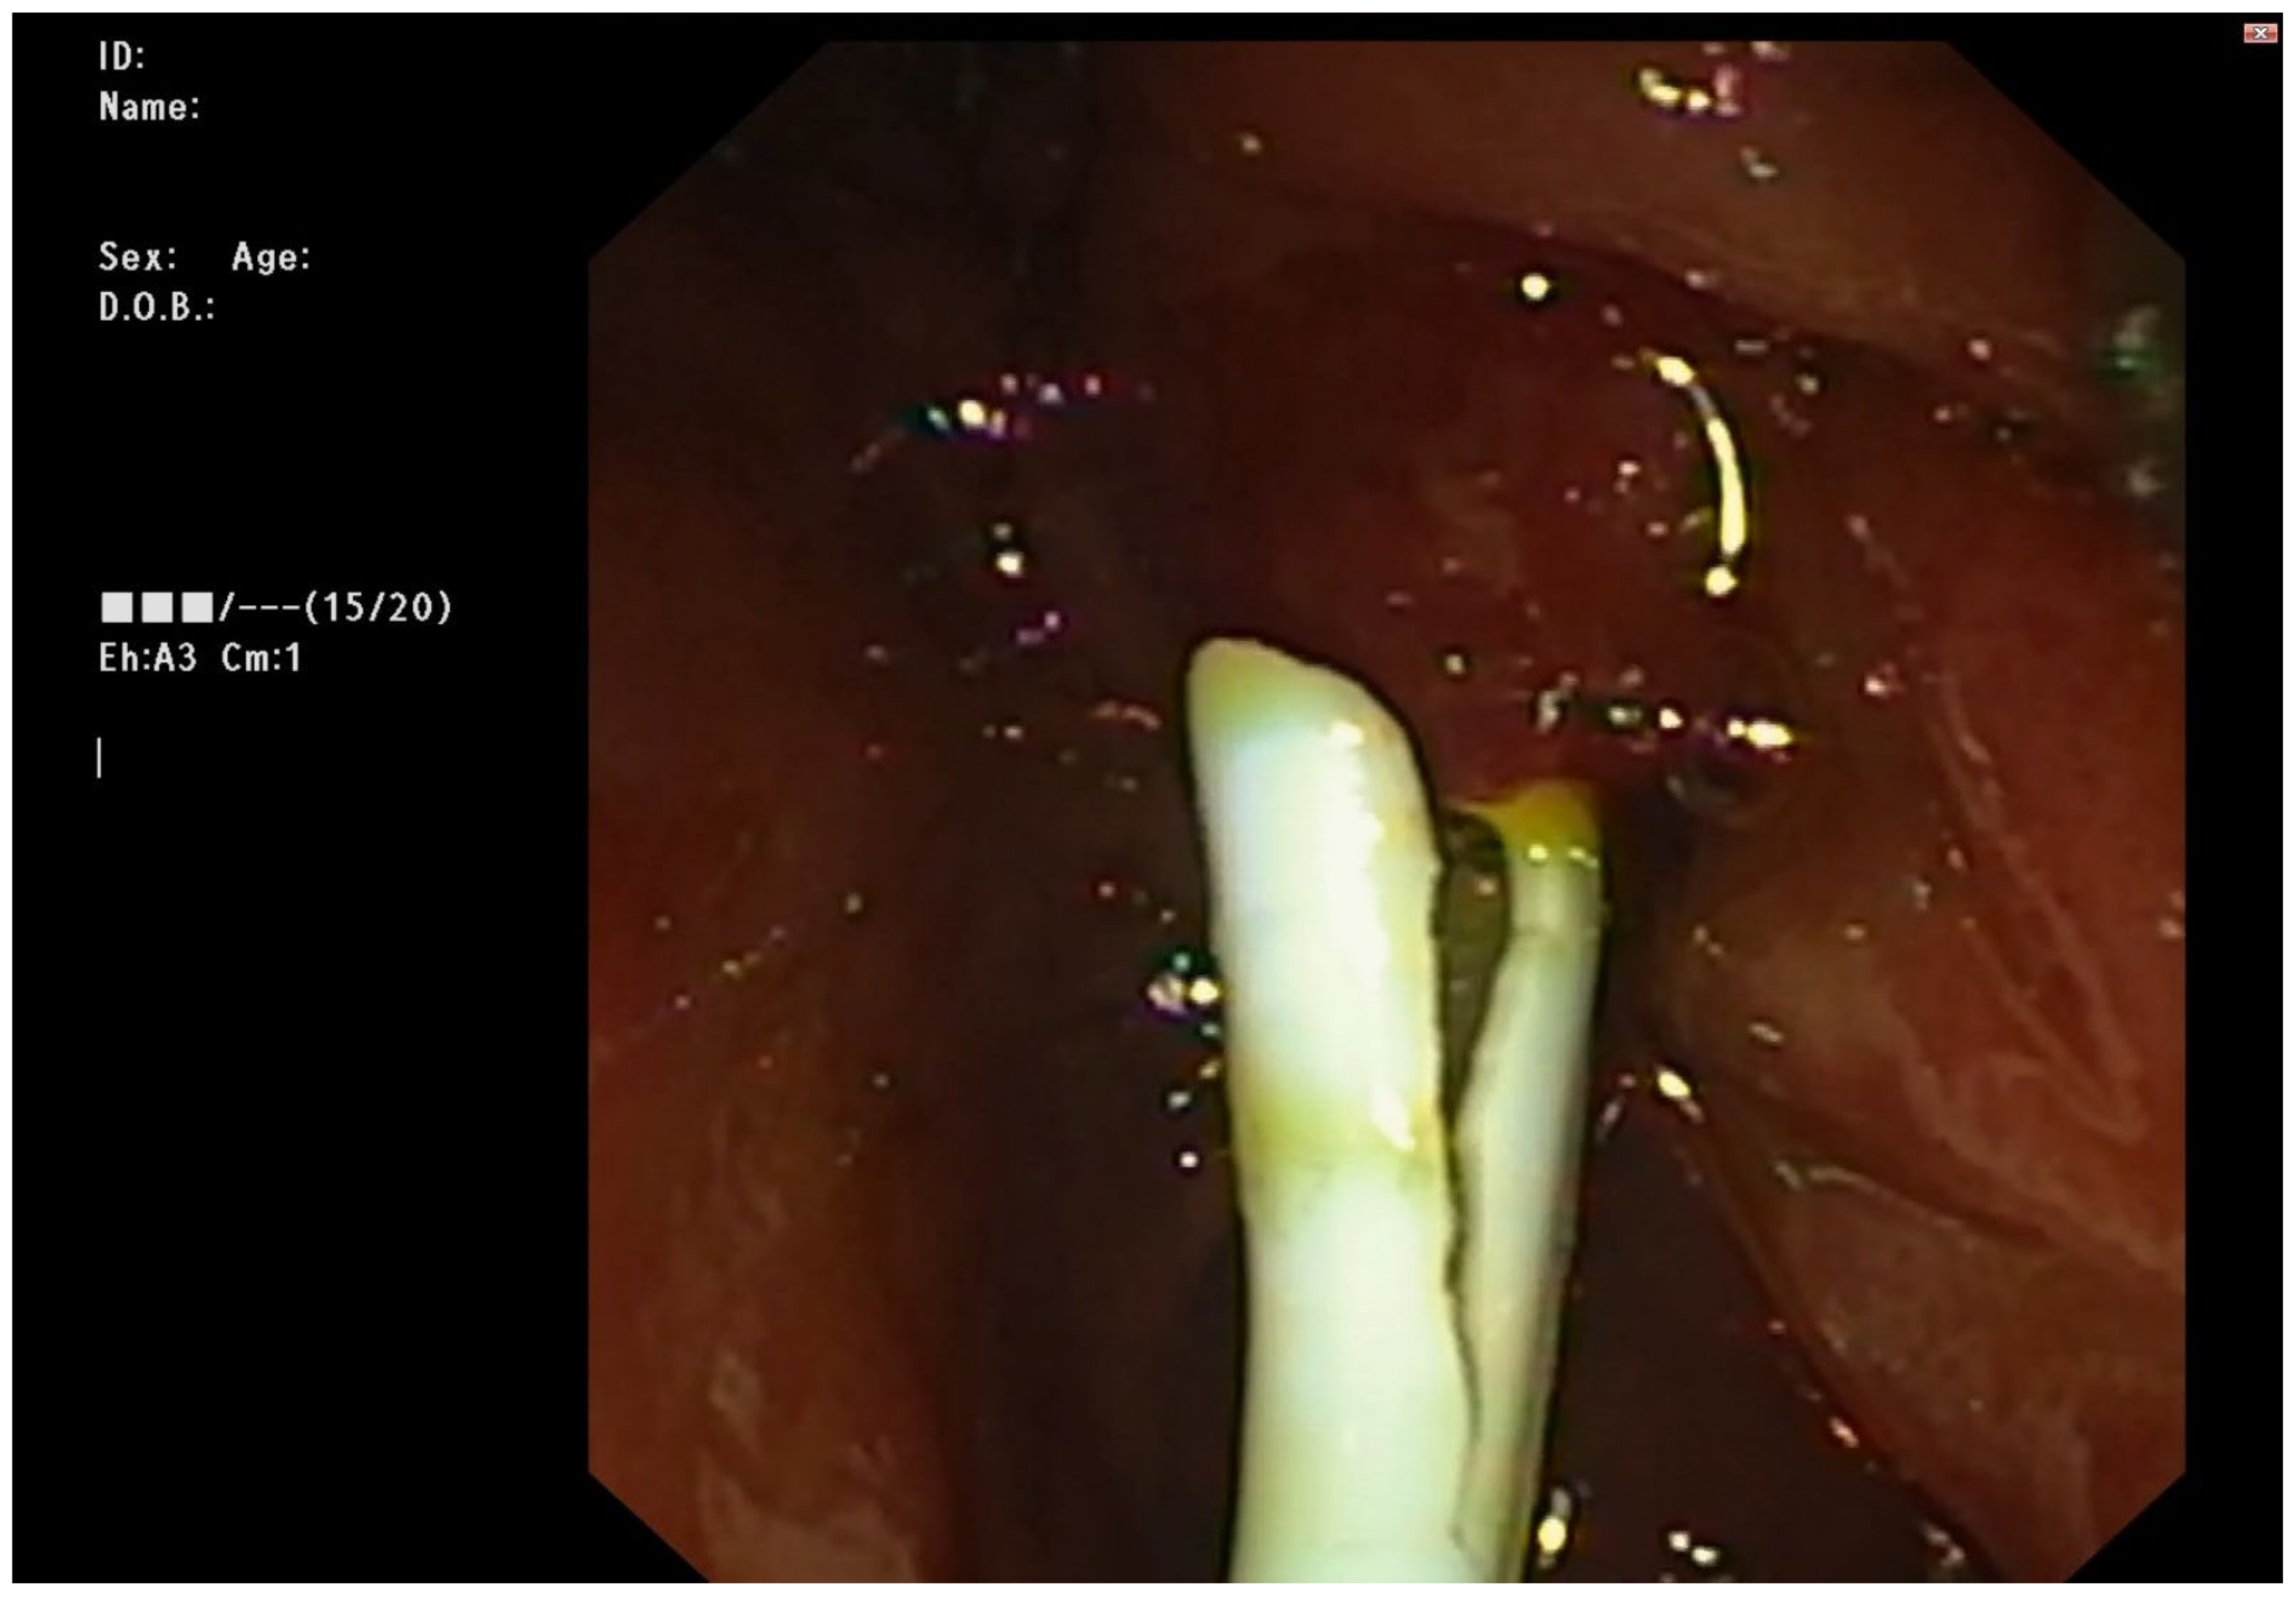

2.3. Endoscopic Management

Figure 3. 1st stent inserted through the fistula with bile flowing.